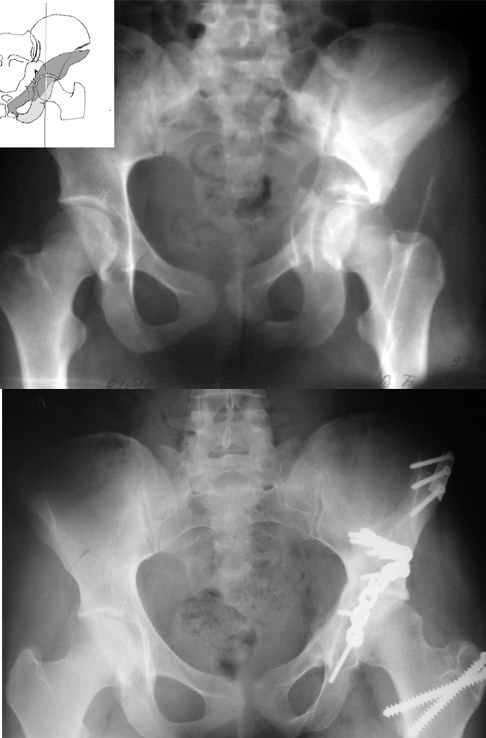

Спасибо за комментарии и рекомендации. Откровенно говоря, больного я прооперировал на прошлой неделе, через 5 дней после аварии и проблем с ним пока никаких нет, на удивление при достаточно обширной диссекции (илиофеморальный доступ) болей практически нет, так что больной самостоятельно садится в кровати, выполняет активные движения в оперированном суставе, сгибая до 60 градусов пока, далее с ассистенцией.

Причиной обращения к сообществу были возникшие непосредственно после операции сомнения и разочарования полученным качеством репозиции: а надо ли было трогать перелом вообще, репозиция передней колонны технически была очень сложна для меня, хотя реконструкции была в той же последовательности, что Д-р А.В.Рунков рекомендовал, в какой-то момент безуспешных манипуляций стал думать о *вторичной конгруэнтности*, которую не так давно обсуждали на

форуме и скелетном вытяжении. С репозицией и фиксацией задней колонны и отдельно задне-верхней стенки впадины проблем не возникло. Послеоп. Рг граммы в приложении. Если возникнут какие-либо дополнения или поправки - был бы признателен.